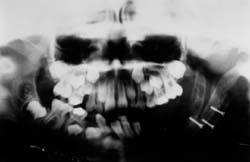

• Al control radiográfico se evidencia oseointegración entre el injerto costocondral con el segmento distal del maxilar, así mismo se evidencia a nivel del proceso condral de la costilla zona radiolúcida compatible con zonas de remodelado óseo.

• Se observa limitación de las excursiones laterales, no se ha considerado un agravante ante la evolución, debido a que hace relación a la fisiología y remodelación comportamental de los injertos costocondrales. (Fig. 5-6)